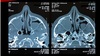

Estudio de imagen que se solicita para sinusitis

Tomografía de nariz y senos paranasales

*Gold standard

En que px se indica la TC para sinusitis

Oncológicos, inmunosuprimidos y sinusitis crónica